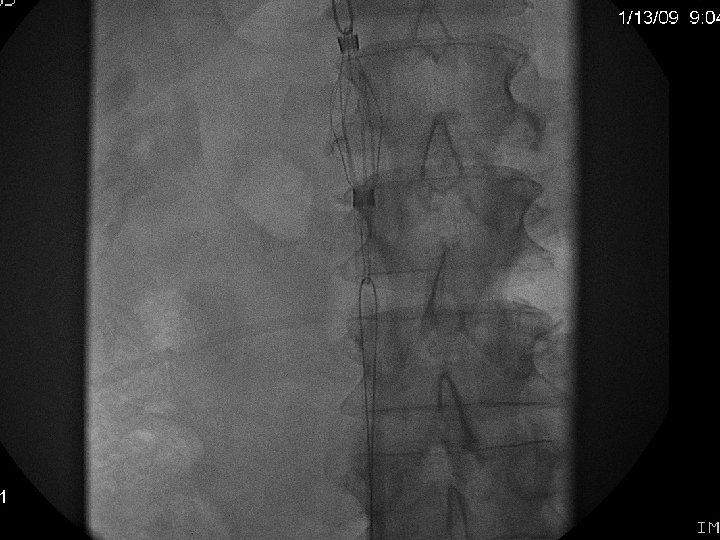

Retrieval with a “grasping”device Recovery Filter, G 2 (Bard Peripheral Vascular) Aln (Aln Implants)

G 2 Filter Cone Bard Peripheral Vascular.

Bard Peripheral Vascular.

Recovery (G 2) Retrieval